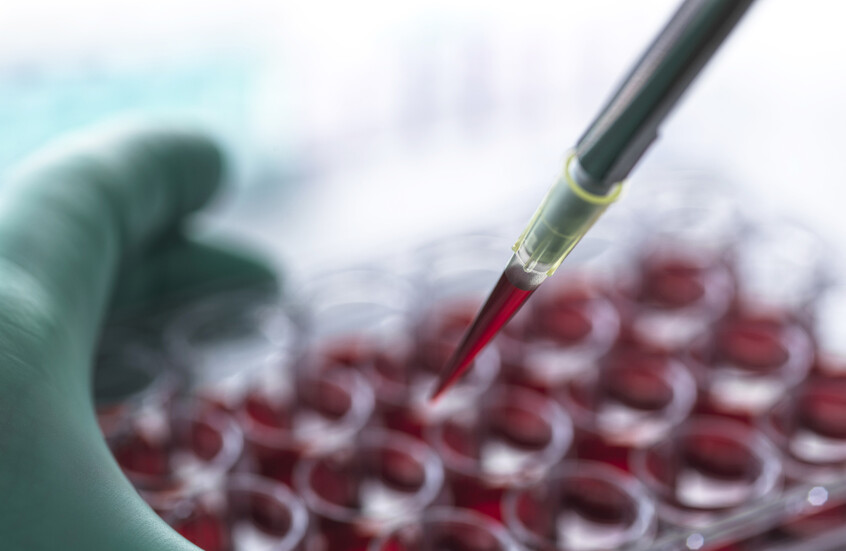

ما هي علامات الإصابة بسرطان الغدة الدرقية وهل يمكن علاج المرض؟

يعد سرطان الغدة الدرقية نوعا نادرا من السرطانات، ويؤثر على الغدة الدرقية، وهي غدة صغيرة في قاعدة العنق تنتج الهرمونات وتلعب دورا في التمثيل الغذائي والنمو والتطور.

ويعرف أن هذا النوع من السرطان شائع بين الأشخاص في الثلاثينيات من العمر والذين تزيد أعمارهم عن 60 عاما، كما أن النساء أكثر عرضة للإصابة به مرتين إلى ثلاث مرات أكثر من الرجال.

ويتمثل العارض الرئيسي لسرطان الغدة الدرقية في وجود كتلة في مقدمة العنق تكون عادة غير مؤلمة أو منتفخة.

وإذا وجدت تورما في رقبتك، فلا داعي للذعر لأن كتلة واحدة فقط من بين كل 20 كتلة في الرقبة يمكن أن تكون سرطانية.

والكتل في الرقبة شائعة وغالبا ما تكون أقل خطورة، ولكن إذا كانت التكتل صلبة، ولا تتحرك بسهولة ويبدو أنها تكبر بمرور الوقت، فمن المرجح أن تكون سرطانا.

ويقول موقع هيئة الخدمات الصحية الوطنية البريطانية (NHS) إنه يجب عليك زيارة طبيب عام إذا كان لديك أي تورم في مقدمة عنقك على الرغم من أنه من غير المحتمل أن يكون سرطانا.

وقد تصاحب الورم أعراض أخرى، بما في ذلك تورم الغدد، وبحة في الصوت، والتهاب الحلق، وألم في الرقبة، وصعوبة في البلع، وصعوبة في التنفس، وأحيانا إسهال واحمرار.

ويحدث سرطان الغدة الدرقية عندما يكون هناك تغيير في الحمض النووي داخل خلايا الغدة الدرقية وتبدأ في النمو دون حسيب ولا رقيب وتنتج كتلة.

ومن الصعب معرفة سبب هذا التغيير، ولكن هناك القليل منها يمكن أن يزيد من خطر حدوث هذا التغيير مثل أمراض الغدة الدرقية الأخرى، والتاريخ العائلي لسرطان الغدة الدرقية، والإشعاع، والسمنة، والورم الغدي العائلي.

ويمكن الوقاية من حالة واحدة تقريبا من كل 10 (9%) من الحالات، لذا من المهم تقليل المخاطر حيثما أمكن من خلال اتباع أسلوب حياة صحي وعدم التدخين.

هل يمكن علاج سرطان الغدة الدرقية؟

عادة ما يتم علاج سرطان الغدة الدرقية، ويمكن علاج العديد من الحالات بشكل كامل، وفقا لهيئة الخدمات الصحية الوطنية.

ومن بين جميع حالات سرطان الغدة الدرقية، يعيش 84% من سرطان الغدة الدرقية لمدة 10 سنوات أو أكثر.

وتشمل العلاجات الرئيسية لسرطان الغدة الدرقية الجراحة لإزالة جزء أو كل الغدة الدرقية، والعلاج باليود المشع، والعلاج الإشعاعي الخارجي والعلاج الكيميائي أو العلاجات المستهدفة.

وبمجرد الانتهاء من العلاج، من المهم حضور مواعيد المتابعة لأن سرطان الغدة الدرقية يمكن أن يعود في بعض الأحيان بعد العلاج.

وإذا تمت إزالة الغدة الدرقية كجزء من العلاج، فلن يعود بإمكان جسمك إنتاج هرمون الغدة الدرقية، وعادة ما يتناول هؤلاء الأشخاص حبوبا يومية تحتوي على هرمون الغدة الدرقية الاصطناعية لضمان عدم ظهور أعراض قصور الغدة الدرقية مثل التعب والحساسية تجاه البرد وزيادة الوزن والإمساك والاكتئاب وهشاشة الشعر والأظافر، بالإضافة إلى الحركات والأفكار البطيئة وآلام العضلات وتشنجاتها وضعفها وأكثر من ذلك.

ويمكن للناس أن يعيشوا حياة كاملة وطويلة دون الغدة الدرقية طالما أنهم يتناولون أدويتهم ويستمرون في مراجعة الطبيب بعد الجراحة.